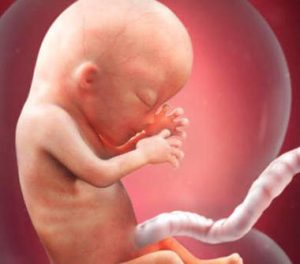

En ny trimester begynder, og det gør også et andet stadium for din lille i din livmoder. I den 13. uge af graviditeten er din babys højde mellem 6,5 – 10 cm, og deres vægt varierer fra 13-20 gram.

Deres ansigt begynder at danne dets unikke egenskaber, blandt andet transformationer, som vi vil gennemgå nedenfor. Det er utroligt spændende!

Ud over den endelige placering af deres øjne og ører er der en virkelig fascinerende detalje: fingeraftrykket er allerede skabt.

Hjernen er en af de mest udviklede dele af fosteret, ligesom de strukturer, der understøtter og dækker organerne.

På dette tidspunkt udgør hovedet halvdelen af fostrets samlede størrelse.

Fra nu af vil kroppen begynde at vokse hurtigere for at indhente og dermed opnå en proportional krop.

Faktisk udgør foden ved fødslen kun en fjerdedel af den samlede størrelse. Derudover er der også et par meget vigtige processer relateret til fostrets krop og dets funktion.